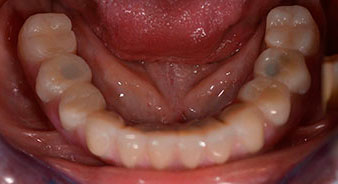

Пациентката е 64-годишна жена с частично обеззъбяване на зъби 38, 33 и 43 и частична долночелюстна протеза (Фиг. 1 и 2).

След това е взет отпечатък и е определена захапката на пациента, за да може зъботехникът незабавно да започне изработването на временната протеза. Протезата е поставена в същия ден (Фиг. 17 и 18).

След изчакване на необходимото време за осеоинтеграция, финалният отпечатък на имплантите е свален и следователно е изработена финалната протеза (Фиг. 19 и 20). В този момент, лекарят по дентална медицина и пациентът могат да обсъдят дали да използват керамични или пластмасови фасети и циркониева или метална рамка. В този случай, екипът на д-р Паску избира пластмасови фасети, имайки предвид неясната прогноза относно частичното обеззъбяване в челюстта и фактът, че зъб 24 е прорастнал. Този вид протеза обикновено е по-лесна за адаптиране и впоследствие може да бъде променяна спрямо новата ситуация в челюстта.